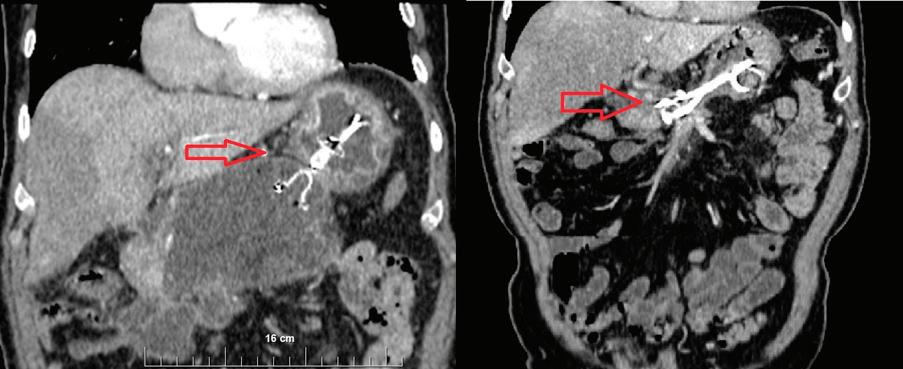

на СА19-9 и карциноембрионален антиген (СЕА) се прилага при пациенти със сус пектен злокачествен процес, като спомага за диагностиката и проследяването му, въпреки че не са специфични маркери за билиарна ма лигненост. При менажирането на такъв тип стенози от из ключителна важност е предварителното ста диране на пациента с образни методи – УЗ, КТ Фиг. 1 Холангиограма на пост оперативна стеноза след холецистектомия Фиг. 2 Холангиоскопски образ при стеноза на анасто мозата след чернодроб на трансплантация чини,

с контраст, магнитно-резонансна хо лангиопанкреатография – неинвaзи вен метод, който не само локализира интрахепаталните жлъчни стриктури (97% точност), но също така позволя ва създаването на карта „billiary map tree“, която да планира ендоскопска та интервенция Ендоскопски метод на избор при диференциална диагноза между бенигнен и малигнен характер на стенозата е ЕРХПГ с холангиоско пия – директна визуализация и оха рактеризиране, с възможност за це ленасочени биопсии и хистологична верификация. Чрез тези методи може да се установи локализацията, видът и протежението на стенозата. Инфор мативността и достоверността на тези два метода (ЕРХПГ и холангиоскопия) е близо до 100%[11] (Фиг. 2). Перкутанната трансхепатална холан гиография и сцинтиграфията в наши дни почти са изгубили диагностична стойност. Ендоскоспската ехография може да бъде полезна по отношение на деферинциална диагноза на ма лигнени лезии, причнияващи билиар на стеноза, както и в определени слу чаи за терапевтичен жлъчен дренаж при бенигнени стриктури на ЖП[1] ЛЕЧЕНИЕ Доброкачествените жлъчни стрик тури са предизвикателство за лече ние. Повечето бенигнени стриктури са свързани с хирургични процеду ри, травматична увреда на жлъчните пътища при чернодробна трансплан тация и лапароскопска холецистек томия, като съобщаваната честота варира съответно между 3 и 13% и меджу 0.2 и 0.7%[12].

Фиг. 3). Металните

имат

пластмасовите (10 срещу 3.3 мм), по-голяма сила на разширява не, технически предимства, тъй като са по-лесни за поставяне и отнемат по-малко време отколкото поставя нето на MPS. По-голямата радиална сила прилага постоянна и най-голя ма сумарна дилатация върху стрикту

ата по време на първоначалната ЕРХПГ, като и позволява по-големи интервали между смя ната на стентовете. Всички SEMS, използвани за ДЖС, са напълно покрити, за да се предо тврати врастването на тъканите и епители зацията на стента в стената на канала, което прави отстраняването възможно. Повечето са направени от политетрафлуоретиленов слой и имат „ласо“ разположени в горния ръб на стента, за да улеснят последващото отстраня ване. Някои СЕМС разпологат с антти-мигра ционни „перки“[18.19] (Фиг. 4). Като цяло, лечението на стриктурата и ре моделирането на жлъчните пътища изглеж да по-бързо със SEMS в определени ситуации в сравнение с MPS, като изисква по-малко от общо 12-те месеца продължителност до смя ната на стента, изисквана при пластмасовите стентове. Смята се, че този съкратен период намалява процен та на усложненията, свързани със стента, особено при отстра няване му, без да се компрометира край ния резултат. Задължително е да се избере правил ният стент за кон кретната индикация и местоположение. Основното определяне на характеристики те се основава на дължината на стриктура та, местоположението и етиологията. SEMS са най-подходящи за свързани с хроничен пан креатит стриктури и някои пост-опреатив ни случаи. Използването на SEMS при хилус ни стриктури не се препоръчва поради риск от смачкване, както и оклузия на интрахепа талните клонове от противоположния лоб, което може да доведе до сепсис. Ако стен тът покрива д. цистикус, може да възникне холецистит, в случай че пациентът има жлъ чен мехур. Освен това SEMS не дават добри резултати при стриктури след холецистек томия и анастомотични стриктури поради прекомерна миграция и рецидив на стрик турите. За разлика от пластмасовите стен тове, по-малко задълбочени проучвания на протоколите за дилатация за SEMS при до брокачествени стриктури са налични. Ос вен това, оптималната продължителност

Фиг. 3

Видове пластмасови стентове Фиг. 4

Напълно покрит метален стент анти-миграционни „перки“ – SEMS Фиг. 5

Холангиграма - стеноза на д.холедохус след хо лецистектомия, поста вен напълно покрит ме тален стент